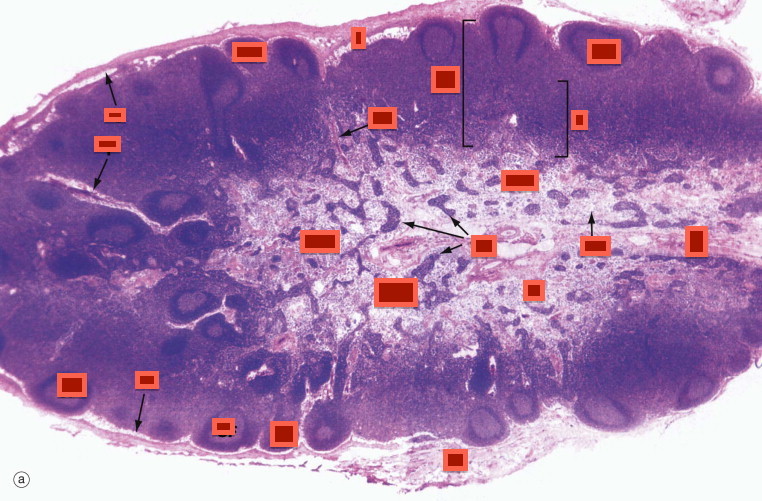

Spleen

White Pulp

Red Pulp

MALT

mucosa associated lymphoid tissue

lumen